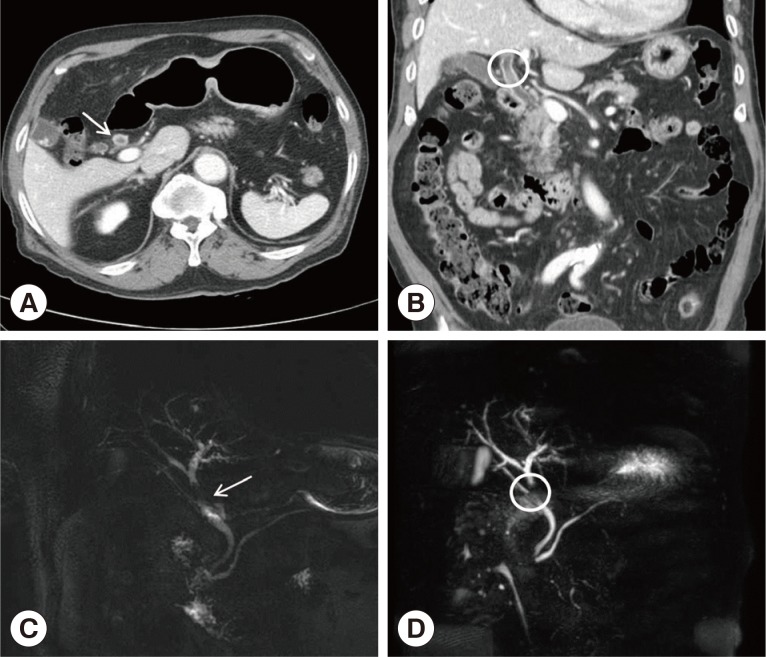

Fig. 1

CT and MRCP findings of intraductal lesion of the present patient. (A) CT showing the segmental common hepatic duct wall thickening (white arrow). (B) Intraductal soft tissue lesion in the common hepatic duct without definite evidence of duct obstruction (white circle). (C, D). MRCP revealing intraductal filling defect of the mid-portion of the common bile duct (white arrow and circle).

Fig. 1 CT and MRCP findings of intraductal lesion of the present patient. (A) CT showing the segmental common hepatic duct wall thickening (white arrow). (B) Intraductal soft tissue lesion in the common hepatic duct without definite evidence of duct obstruction (white circle). (C, D). MRCP revealing intraductal filling defect of the mid-portion of the common bile duct (white arrow and circle).